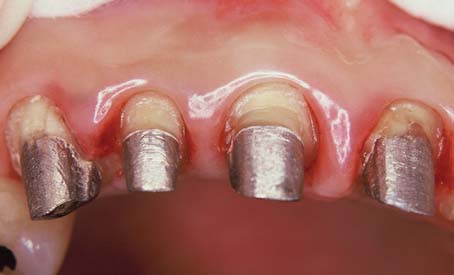

Fig. 12-3 The first molar and second premolar have been restored with post and cores. Note the margins, optimally located on sound tooth structure, cervical to the castings.